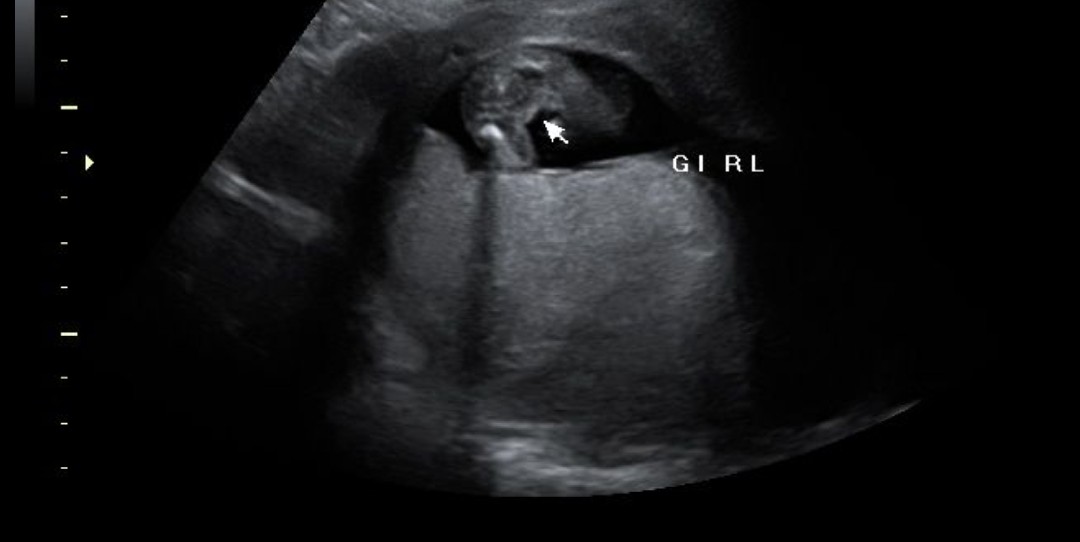

I have 8 boys and 1 girl. Do you think this will be my 2nd girl or 9th boy? 12 weeks 2 days. ThanksAttachment 43210Attachment 43210